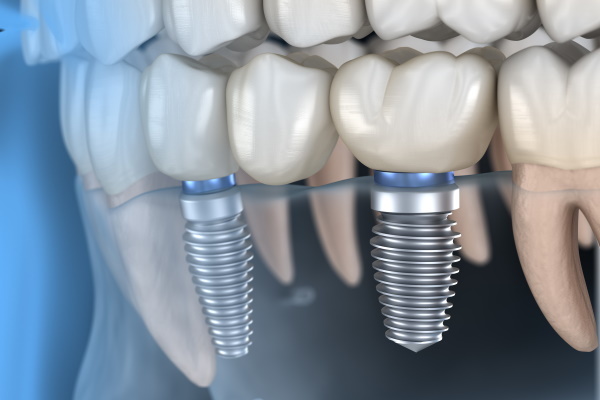

قبل از هرچیز بهتر است به طور مختصر به تعریف خود ایمپلنت بپردازیم. ایمپلنت در لغت به معنی کاشت است. در دندان پزشکی از روش ایمپلنت یا کاشت دندان برای پر کردن جای خالی دندانهای از دست رفته استفاده میشود. گاهی اوقات ممکن است دندانها بر اثر ضربه شدید، پوسیدگیهای عمیق، بیماریهای لثهای، عفونت و... از بین بروند. در چنین مواردی کاشت دندان یا ایمپلنت بهترین روش برای جایگزین کردن این دندانهاست. زیرا پایه ایمپلنت که در استخوان و لثه قرار میگیرد از جنس تیتانیوم بوده که کاملاً با بدن سازگار است و با مقاومت بسیار بالایی که دارد میتواند وظیفه ریشه دندان را به عهده بگیرد.

درمان ایمپلنت به شما این اجازه را میدهد که پس از تکمیل دوره درمان، دندانی طبیعی داشته باشید و بدون نگرانی مثل سابق به خوردن و جویدن ادامه دهید. این روش نسبت به روشهای قدیمی مانند بریج هم میزان موفقیت بیشتر و هم عوارض کمتری برای لثهها و دندانهای مجاور دارد.

قیمت هر واحد ایمپلنت Biotech Dental فرانسه به همراه بهترین نوع روکش موجود در ایران، 19.5میلیون تومان میباشد که شامل فیکسچر ، هیلینگ، اباتمنت، ایمپریشن، کربن هیدروکساید، روکش اصلی (تاج دندان) وتمام مراحل جراحی و لابراتوآر است.

گاهی اوقات برای 3تا4 دندان که در مجاورت هم از دست رفته اند فقط به دو ایمپلنت نیاز است ولی از 4 روکش استفاده میگردد در این شرایط هزینه بیمار معادل دو ایمپلنت و دو روکش است درواقع هزینه بیمار از آنچه تصور دارد و خودشان محاسبه میکنند کمتر خواهد بود(مشابه عکس پائین)